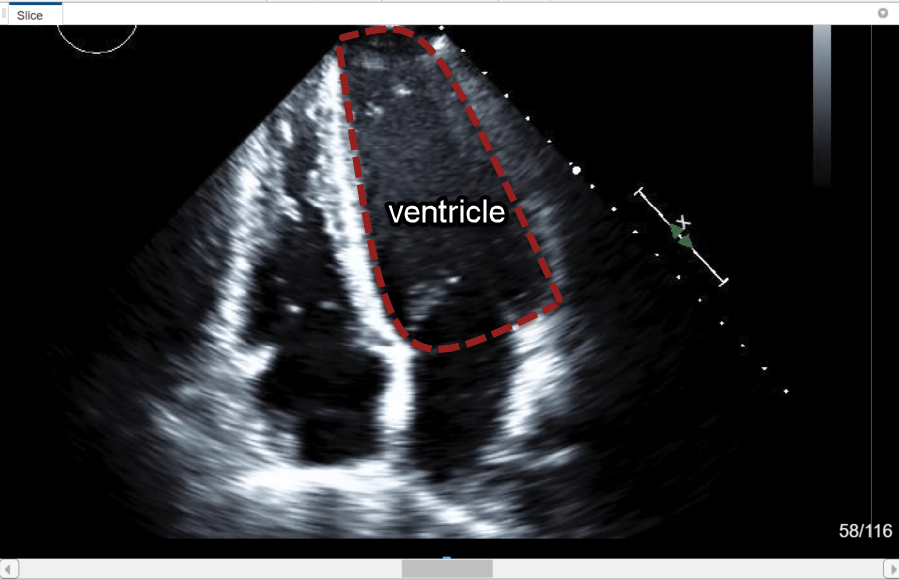

Explore the echocardiogram image series to identify the left ventricle. The annotated image shows the approximate outline of the ventricle to label. Note that all labels in this example have been created for illustrative purposes only and have not been verified by a clinical professional.

Create Label Definitions

A label definition specifies the name, color, and numeric index of a label. In the Label Definitions pane, select Create Label Definition to create a label with the default name Label1. To change the name of the label, click the label and enter a new name. The label name must be a valid MATLAB variable name with no spaces. For this example, specify the name of the label as LeftVentricle. To change the default color associated with the label, click the colored square in the label identifier and select a color from the Color dialog box.